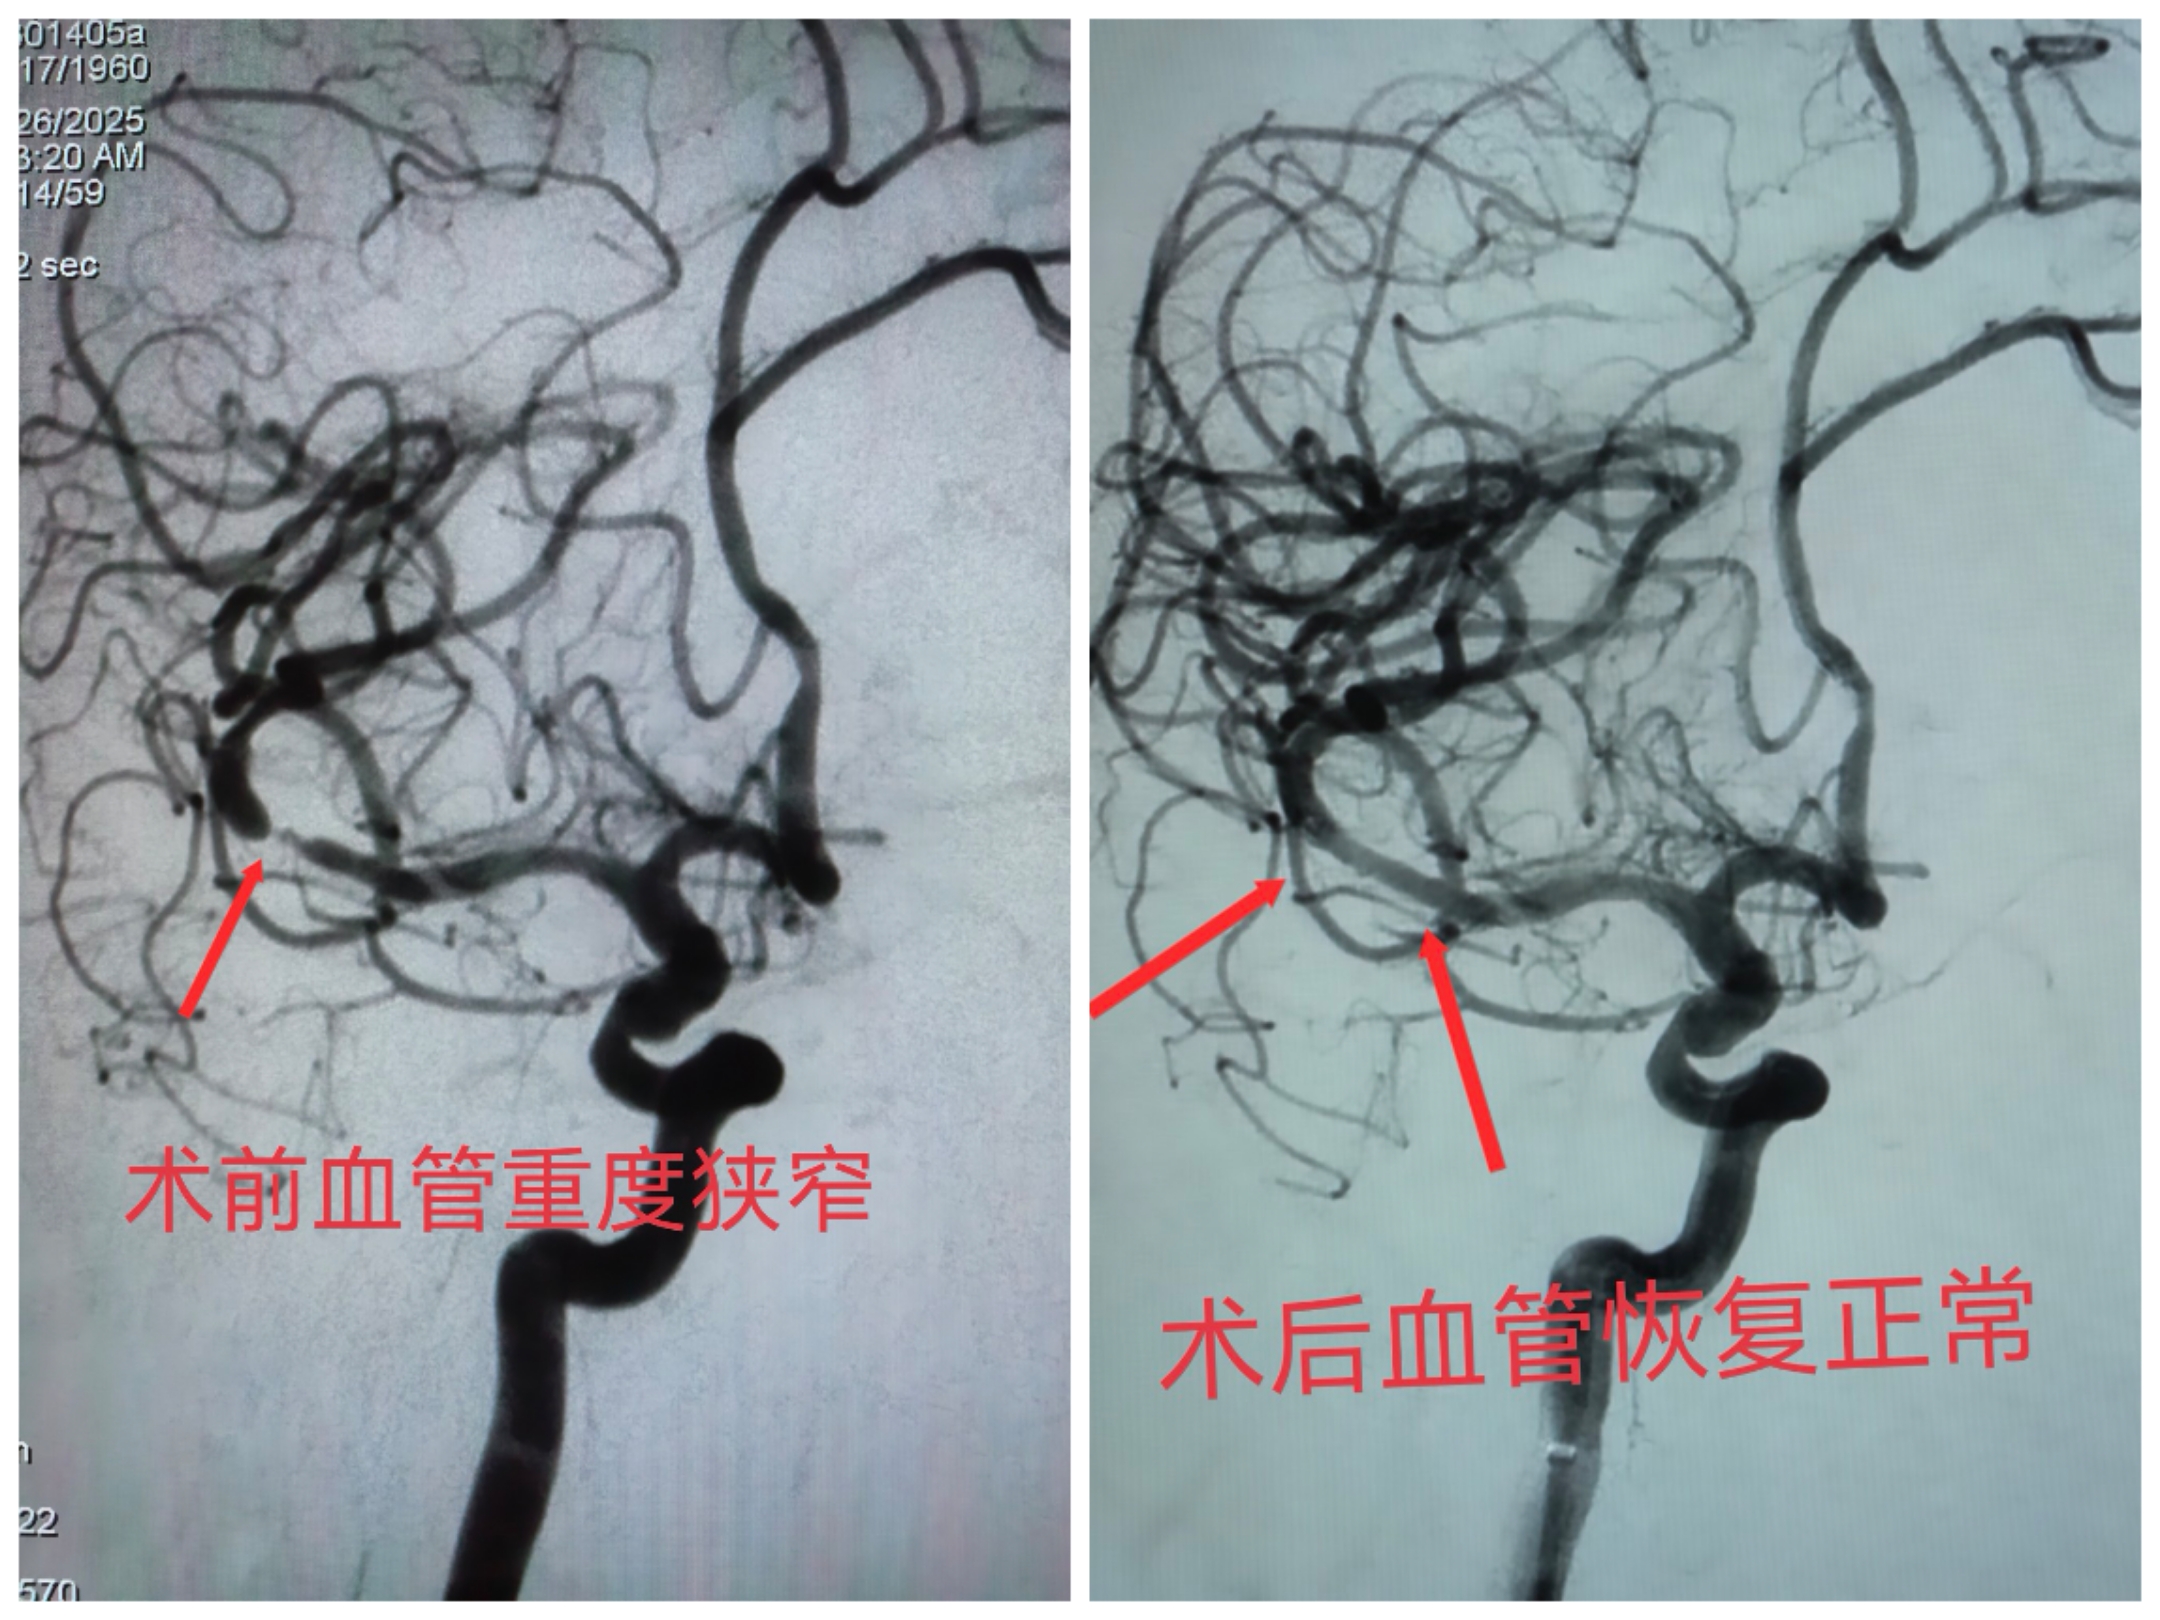

手术当天,在数字减影血管造影系统的精确引导下,神经内科团队如履薄冰又沉稳有序地操作,将一枚微小而柔软的支架精准植入狭窄的血管段。顷刻之间,原本狭窄的血管被成功扩张,血流恢复通畅,大脑供血立时改善。整个手术过程顺利,患者全程保持清醒状态。

经过神经内科团队的细致检查与综合评估,病因终于浮出水面——患者右侧大脑中动脉存在严重狭窄。这条血管是脑部血供的“生命主干道”,一旦完全堵塞,将引发大面积脑梗死,可能导致永久性偏瘫、言语障碍,甚至危及生命。患者此前出现的短暂性肢体无力,正是大脑严重缺血、脑梗死一触即发的危险征兆。